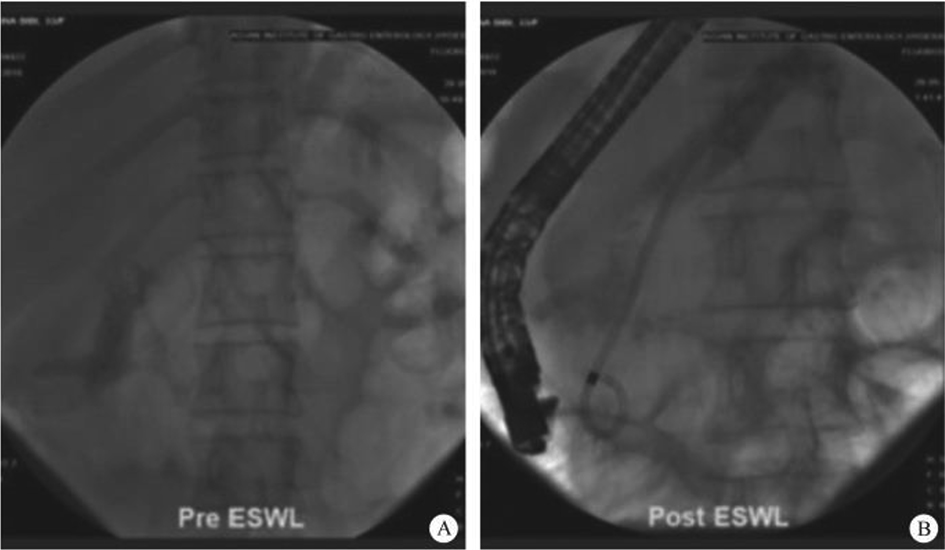

(2) Development of pancreaticobiliary endoscopy: endoscopic retrograde cholangiao-pancreatography (ERCP) has developed steadily for more than half a century, and finally blazed the visible field of the pancreaticobiliary diseases after the emergence of biliary and pancreatic vision equipment, which explored the diagnosis and treatment scope of the endoscope, making precision diagnosis and treatment become a reality. On that basis, a series of SMIS surgeries for biliopancreatic diseases have obtained decisive progress, including laser lithotripsy under direct choledochoscope with preserved sphincter, exploratory pancreatic duct with cholangiopancreatic vision system, super minimally invasive photodynamic therapy under the pancreatic duct, radiofrequency ablation of the bile duct under direct choledochoscope, direct choledochoscopy with a papillary support for cholecystolithiasis and extraction of biliary calculus, etc.

Gastrointestinal endoscopic super minimally invasive surgery (eSMIS) is a branch of SMIS operations. After multiple years of development and clinical practice, presently eSMIS has a perfect endoscopic technique, a nomenclature of procedures and implementation principles, as well as specific development perspectives. Over the recent 10 years, endoscopic scholars in China have been constantly innovating and developing a series of SMIS surgical methods according to four directions, namely, natural, tunnel, puncture, and multi-cavity channels. For example, in the SMIS operation of early gastric cancer, full-thickness resection of the lesion by natural channel, full-thickness resection by multiple-cavity + lymphadenectomy approaches, the technique of sealing large wounds after non-full-thickness resection, and the traction technique in non-full-thickness resection; in the treatment of large-area early esophageal cancer by tunnel channel, autologous skin graft was used to prevent esophageal stenosis after large esophageal defect, and for the diagnosis and treatment through the muscularis propria to the outside of the digestive lumen; some breakthroughs in SMIS operations of the bile pancreatic disease, including laser lithotripsy under direct choledochoscope with sphincter preserved, exploratory pancreatic duct with cholangiopancreatic vision system, super minimally invasive photodynamic therapy under pancreatoscope, radiofrequency ablation of bile duct under direct choledochoscope, direct choledochoscopy with a duodenal papillary support for the extraction of gallbladder silt stones and of biliary calculus, etc., have been achieved.